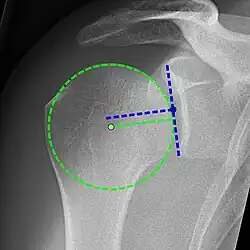

X-ray projectional radiography cannot directly reveal tears of the rotator cuff, a 'soft tissue', and consequently, normal X-rays cannot exclude a damaged cuff. However, indirect evidence of pathology may be seen in instances where one or more of the tendons has undergone degenerative calcification (calcific tendinitis). The humeral head may migrate upward (high-riding humeral head) secondary to tears of the infraspinatus, or combined tears of the supraspinatus and infraspinatus.[51] The migration can be measured by the distance between:

- A line crossing the center of a line between the superior and inferior rims of the glenoid articular surface (blue in image).

- The center of a "best-fit" circle positioned over the humeral articular surface (green in image)

Normally, the former is positioned inferiorly to the latter, and a reversal therefore indicates a rotator cuff tear.[51] Prolonged contact between a high-riding humeral head and the acromion above it may lead to X-ray findings of wear on the humeral head and acromion; secondary degenerative arthritis of the glenohumeral joint (the ball and socket joint of the shoulder), called cuff arthropathy, may follow.[50] Incidental X-ray findings of bone spurs at the adjacent acromioclavicular joint may show a bone spur growing from the outer edge of the clavicle downward toward the rotator cuff. Spurs may also be seen on the underside of the acromion, once thought to cause direct fraying of the rotator cuff from contact friction, a concept currently regarded as controversial.